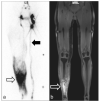

Background: Clinical examination and lymphoscintigraphy are the current standard for investigating lymphatic function. Magnetic resonance imaging (MRI) facilitates three-dimensional (3D), nonionizing imaging of the lymphatic vasculature, including functional assessments of lymphatic flow, and may improve diagnosis and treatment planning in disease states such as lymphedema.

Results: From 612 identified articles, 43 articles were included and their protocols and results summarized. Field strength was 1.5 or 3.0 T in all studies, with 25/43 (58%) employing 3.0 T imaging. Most commonly, imaging of the peripheries, upper and lower limbs including the pelvis (32/43, 74%), and the trunk (10/43, 23%) is performed, including two studies covering both regions. Imaging protocols were heterogenous; however, T2 -weighted and contrast-enhanced T1 -weighted images are routinely acquired and demonstrate the lymphatic vasculature. Edema, vessel, quantity and morphology, and contrast uptake characteristics are commonly reported indicators of lymphatic dysfunction.